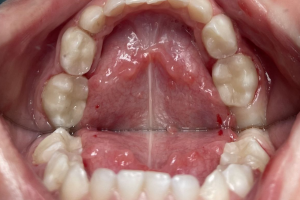

Семейная областная стоматология "Кидди Дентал" - это команда компетентных врачей, каждый из которых знает и любит свое дело. Опыт наших врачей, использование современного оборудования и надежных материалов позволят проводить лечение любой сложности.